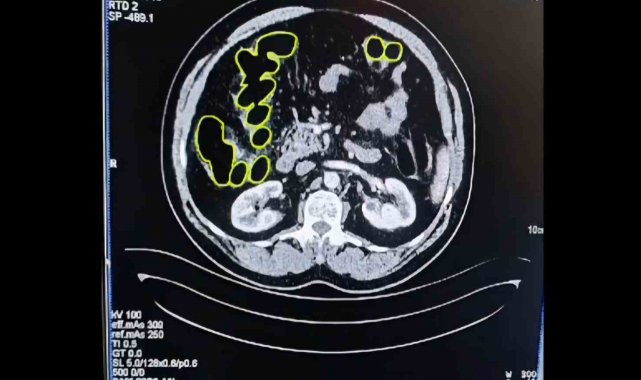

Şüphelilerin Kayseri Şehir Hastanesinde iç beden muayenesine alınırken, mide ve bağırsaklarında da çok miktarda kapsül şeklinde uyuşturucu olduğu değerlendirilen yabancı maddeler tespit edildi.

Mide ve bağırsaklarından uyuşturucu çıktı